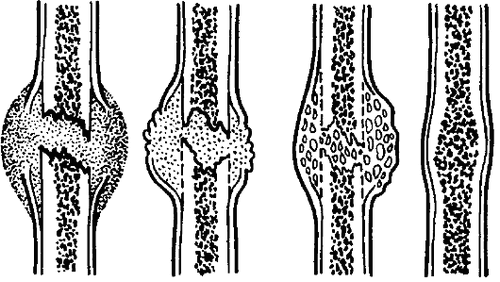

У процесі регенерації виділяють чотири основні стадії:

- Стадія аутолиза. При впливі травмуючого фактора на кістку розвивається набряк поруч розташованих тканин, крім цього, активується частина лейкоцитів, які мігрують в місце травми кістки, в результаті чого загинули клітини і тканини піддаються процесу аутолізу. Перша стадія досягає свого метаболітного піку до 3-4 дня після травми кістки, а потім відбувається її поступове стихання,

- Стадія проліферації. У цей період відбувається активне розмноження клітин кісткової тканини і вироблення активних речовин для побудови мінеральної частини кістки. У деяких пацієнтів при несприятливих умовах спочатку формується хрящова тканина, а потім вона просочується великою кількістю мінеральних речовин і таким чином замінюється кістковою,

- Стадія перебудови кісткової тканини. У хворого поступово відбувається відновлення кровопостачання пошкодженої кістки. У цій стадії у людини з дрібних кісткових балок формується дуже щільне і компактне речовина кістки,

- Стадія повного відновлення. У пацієнта відновлюється структура кістковомозкового каналу. На цій стадії відбувається зміна орієнтації кісткових балок, вони розташовуються відповідно до ліній силових навантажень на кость.Процесс закінчується формуванням окістя і проростанням її новими кровоносними судинами, а також поступовим відновленням всіх морфофункціональних можливостей пошкодженої ділянки кісткової тканини.